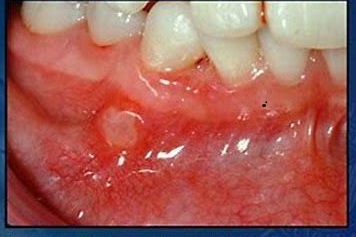

✅ درمان های گیاهی در دندانپزشکی:درمان آفت و زخم های دهان

درمان آفت و زخمهای دهان